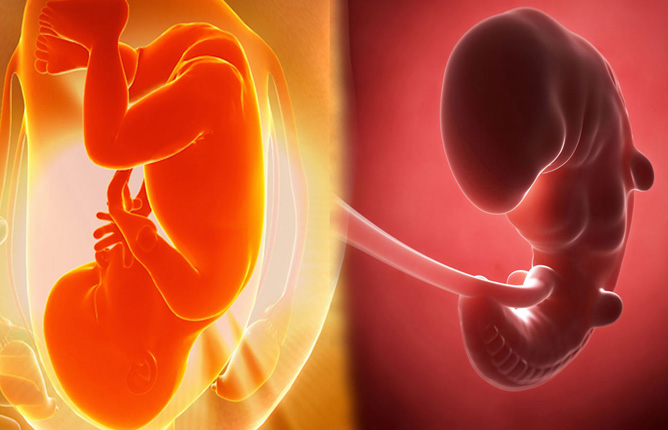

Obstetric Care

Antenatal (pregnancy) checkups

High-risk pregnancy management

Labor and delivery support

Postnatal care and counseling